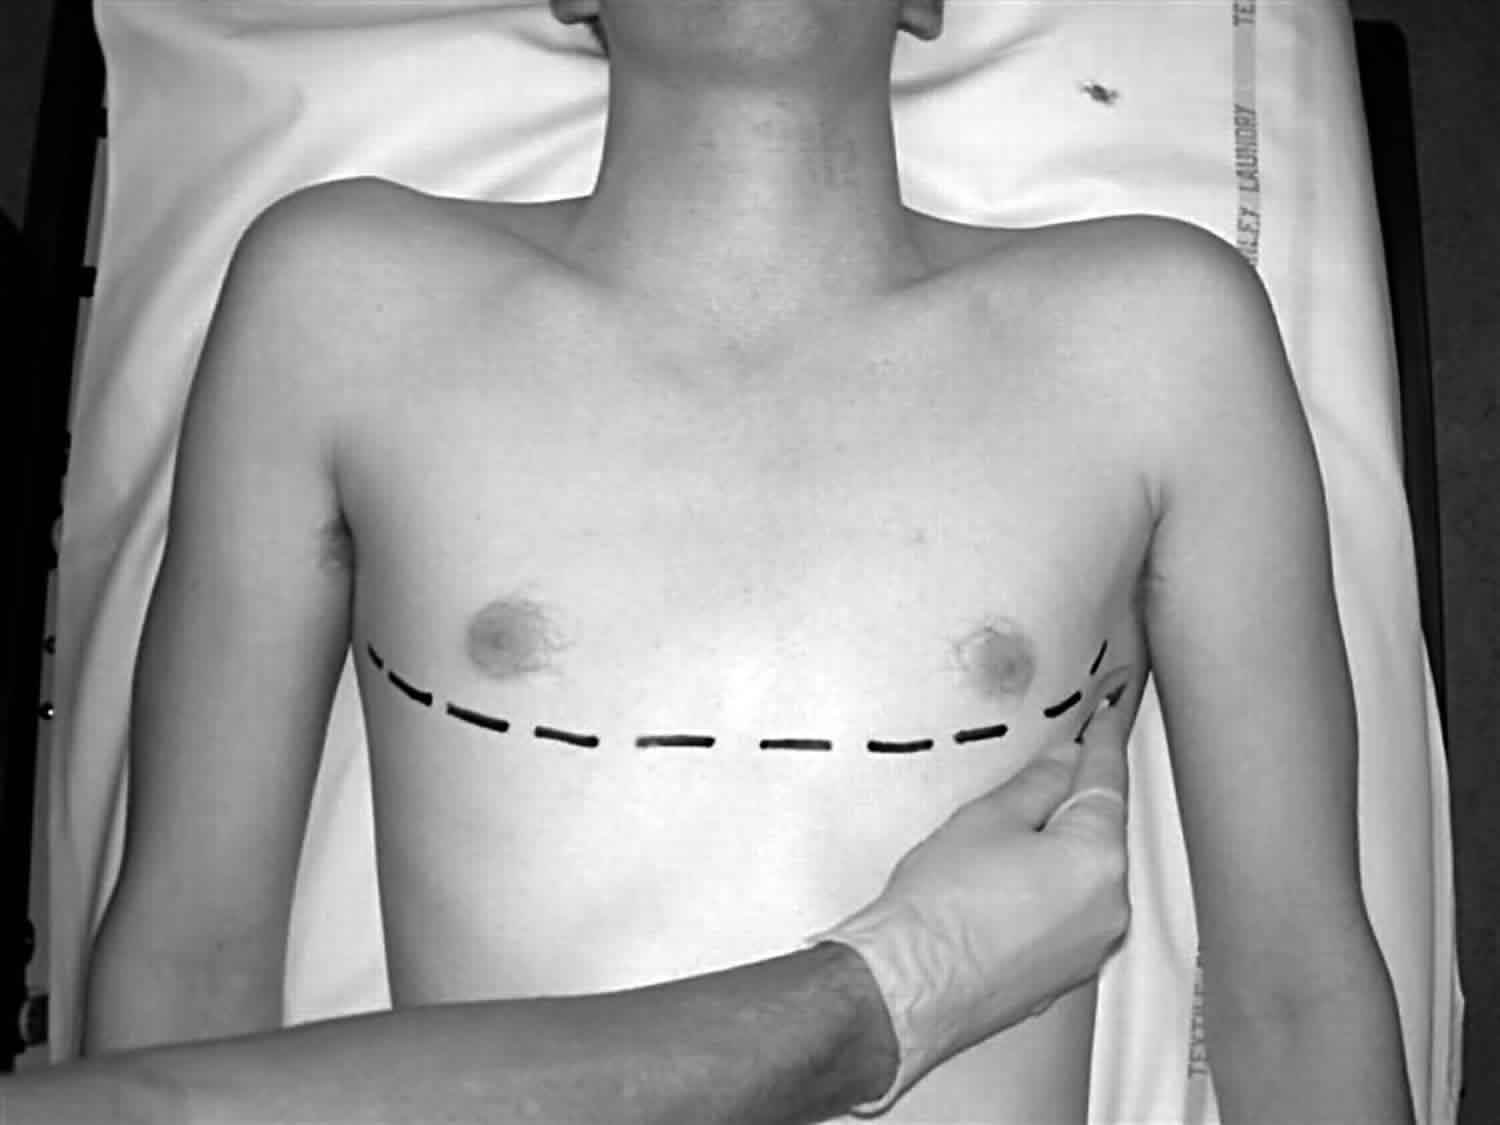

Clamshell thoracotomy is a large transverse incision that spans across the entire chest wall 1. It is also known as a bilateral thoracotomy and is used during massive chest trauma, lung transplant, or resection of tumors in the chest. The incision extends through the sternum, between the fourth and fifth ribs bilaterally, and extends to the mid-axillary line. Mammary vessels will be interrupted as well as intercostal muscles with associated intercostal nerves and vessels 2.

Figure 1. Clamshell thoracotomy

Incision over the fifth rib with dissection into the fourth intercostal space provides the best access to the heart and great vessels. This incision is just beneath the nipple in men or along the inframammary fold in women.